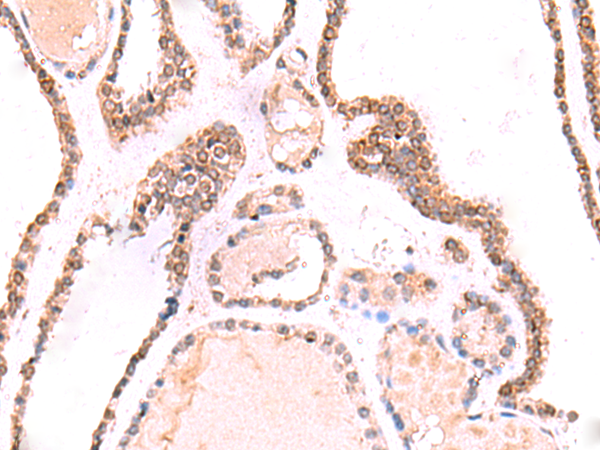

IHC positive control: |

Human thyroid cancer |

IHC Recommend dilution: |

50-300 |